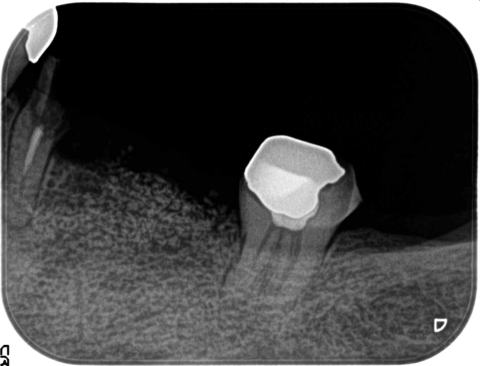

造骨前のレントゲン写真

インプラント植立前に、骨の量を垂直+頬舌方向に高く太くします。